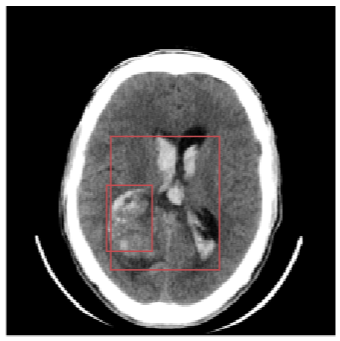

Inverse Problems in Radiology